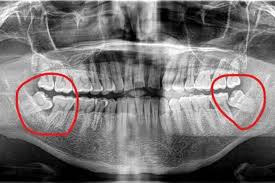

There is a situation where when you have a toothache, you go to the hospital for a check-up and find out that it may be because of impacted wisdom teeth. (The other three wisdom teeth may also be impacted and push against the adjacent teeth, but they are not injured yet. Condition)

Impacted wisdom teeth can cause several types of harm when they grow later.

1. When impacted wisdom teeth grow, they injure adjacent teeth. The dental nerve becomes infected and inflamed, causing severe pain. The dental nerve dies, and the periodontium may be sealed.

Treatment method: First remove the impacted wisdom tooth on the painful side (possibly both the upper and lower teeth), and then perform root canal treatment on the adjacent teeth. (The doctor may arrange to remove one or two wisdom teeth on the other side while removing the sutures. Impacted wisdom teeth only)

2. When impacted wisdom teeth grow, the roots of adjacent teeth are squeezed and broken, and the dental nerves become infected and inflamed, causing severe pain. The adjacent teeth cannot be reworked and can only be extracted.

Treatment method: After the adjacent teeth and the impacted wisdom teeth (possibly both the upper and lower teeth) are removed together, (the doctor may arrange to remove one or two impacted wisdom teeth on the other side while removing the sutures) and wait three months to see the adjacent teeth. Based on the healing of the frontal bone, dental implants can be used to replace the adjacent teeth.

3. A deep blind pocket will be formed between the impacted wisdom teeth and the surrounding gums, which can easily cause food residues to stick to the tooth surface, thereby accumulating for a long time, gradually forming bacterial infection, and deep caries can reach Deep in the dentin, close to the pulp, or may have affected the pulp, causing severe pain.